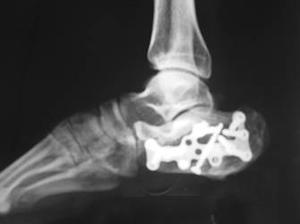

跟骨骨折为成年人较多发生,常由高处坠下或挤压致伤。经常伴有脊椎骨折,骨盆骨折,头、胸、腹伤,初诊时切勿遗误。跟骨为松质骨,血循供应比较丰富,骨不连者甚少见。但如骨折线进入关节面或复位不良,后遗创伤性关节炎及跟骨负重时疼痛者很常见。